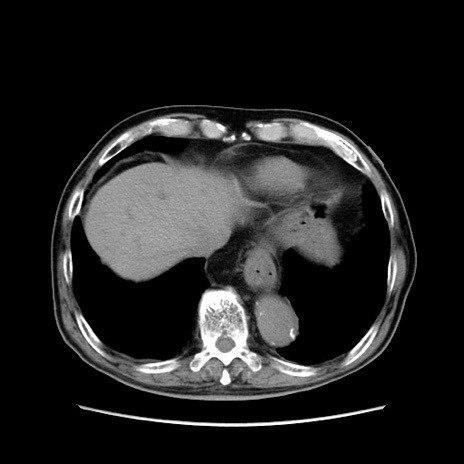

症例24(横断像)

【症例】80歳代男性

【主訴】左側腹部痛、嘔吐

【現病歴】本日早朝より左腹部に痛みあり。昼頃嘔吐認めたため、救急要請。

【既往歴】直腸癌(Mile手術)、胆摘

【身体所見】意識清明、BT 35.9℃、BP 221/93mmHg、SpO2 97%(RA) 、腹部:左ストーマ周囲に限局性の腹部膨隆あり。 膨隆部自発痛・圧痛あり・軟。

【データ】WBC 7700、CRP 0.09